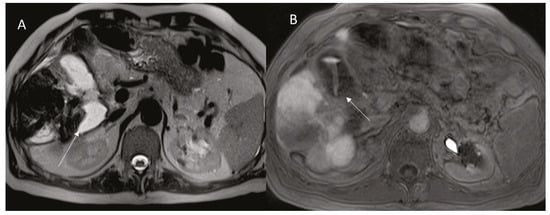

2.3. Pseudoaneurysm